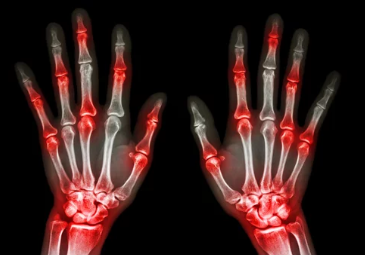

2. 통풍의 주요 증상 – 몸이 보내는 신호들

통풍은 갑작스럽게 발생하는 극심한 통증과 염증이 특징입니다. 초기에는 경미한 증상으로 시작될 수 있으나, 시간이 지나면서 증상이 심화될 수 있습니다.

주요 증상

- 급성 통증: 특히 밤에 발작적으로 발생하며, 관절 부위가 뜨겁고 민감해집니다.

- 부종과 발적: 관절 주변이 붓고 붉게 변합니다.

- 운동 제한: 통증과 부종으로 인해 관절의 움직임이 제한됩니다.

주요 발병 부위

- 엄지발가락(주로 첫 번째 발가락 관절)

- 발목

- 무릎

- 손목 및 손가락 관절